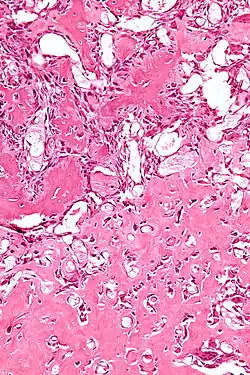

| Micrograph of an osteoblastoma H&E stain | |

The cause of osteoblastoma is unknown. Histologically, osteoblastoma are similar to osteoid osteomas, producing both osteoid and primitive woven bone amidst fibrovascular connective tissue, the difference being that osteoblastoma can grow larger than 2.0 cm in diameter while osteoid osteomas cannot. Although the tumor is usually considered benign, a controversial aggressive variant has been described in the literature, with histologic features similar to those of malignant tumors such as an osteosarcoma.[4]